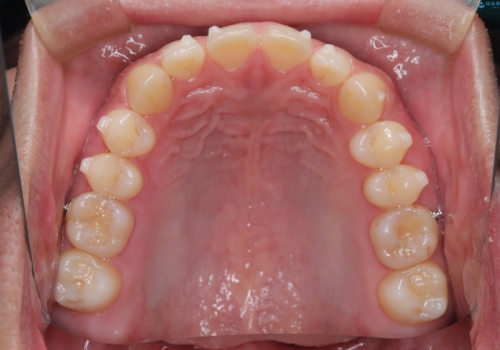

前歯の隙間が気になる マウスピース矯正

- 前歯がすきっ歯であることを気にされて来院された患者様です。上下顎のアーチを整える治療計画を立案し、マウスピースにて治療しました。とてもまじめに使用していただき、気になっていた隙間も順調に閉鎖しました。